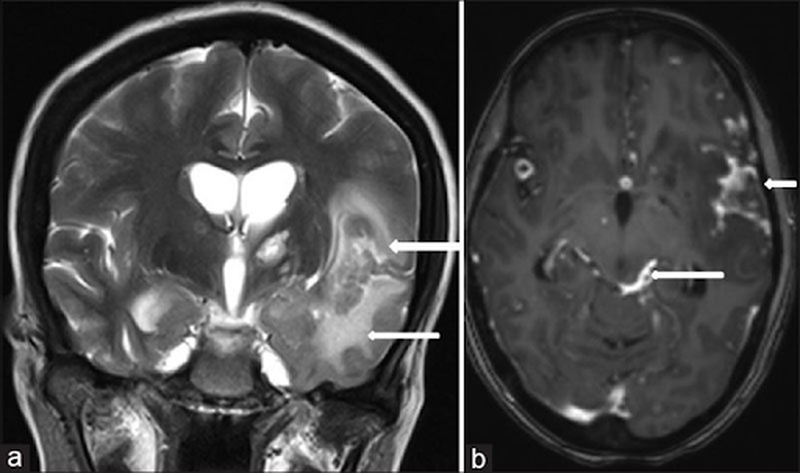

Lao màng não giai đoạn cuối có thật sự nguy hiểm? 3 Hình ảnh chụp CT của người mắc lao màng não giai đoạn cuối